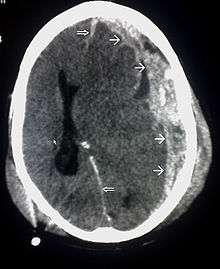

| CT scan showing cerebral contusions, hemorrhage within the hemispheres, subdural hematoma, and skull fractures[1] | |